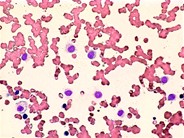

Reactive Histiocytes in the Peripheral Blood - 3.

This cell has a foamy appearance to the cytoplasm.